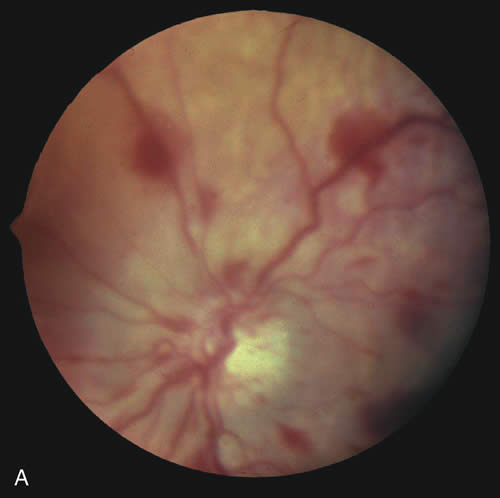

Fig. 8. A. and B. Recurrent chemical injuries inflicted by the father resulted in corneal scarring and vascularization that blinded this 6-year-old girl. (Taylor D, Bentovim A: Recurrent nonaccidentally inflicted chemical eye injuries to siblings. J Pediatr Ophthalmol Strabismus 13:238, 1976.)